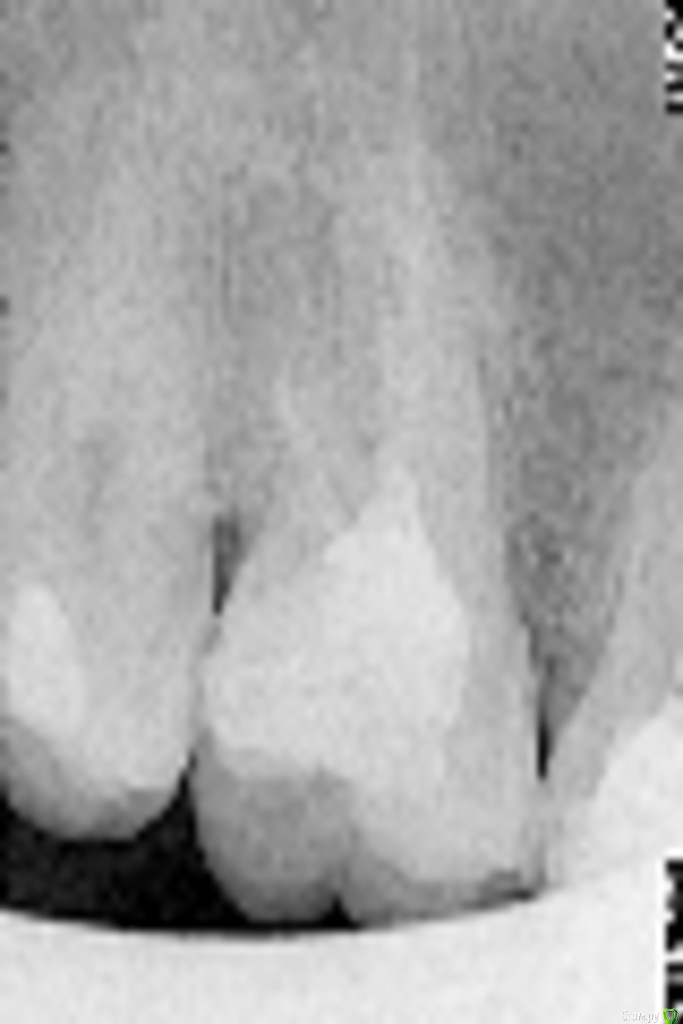

Helen22 Опубликовано 13 декабря, 2015 Автор Поделиться Опубликовано 13 декабря, 2015 Вот ещё прицельные снимки Ссылка на комментарий

Helen22 Опубликовано 13 декабря, 2015 Автор Поделиться Опубликовано 13 декабря, 2015 . Ссылка на комментарий